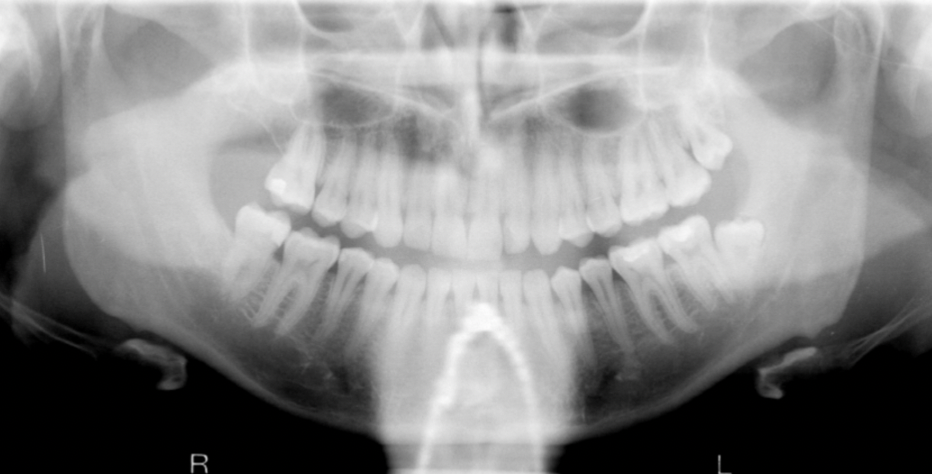

What are some errors that can be seen on this radiograph? What is the cause?

1. flat occlusal plane or reverse curvature 2. roots of maxillary anterior teeth are blurred 3. rami/condyles tipped laterally 4. condyles close to or cut off side of image 5. hard palate superimposed on maxillary apices Cause: chin up